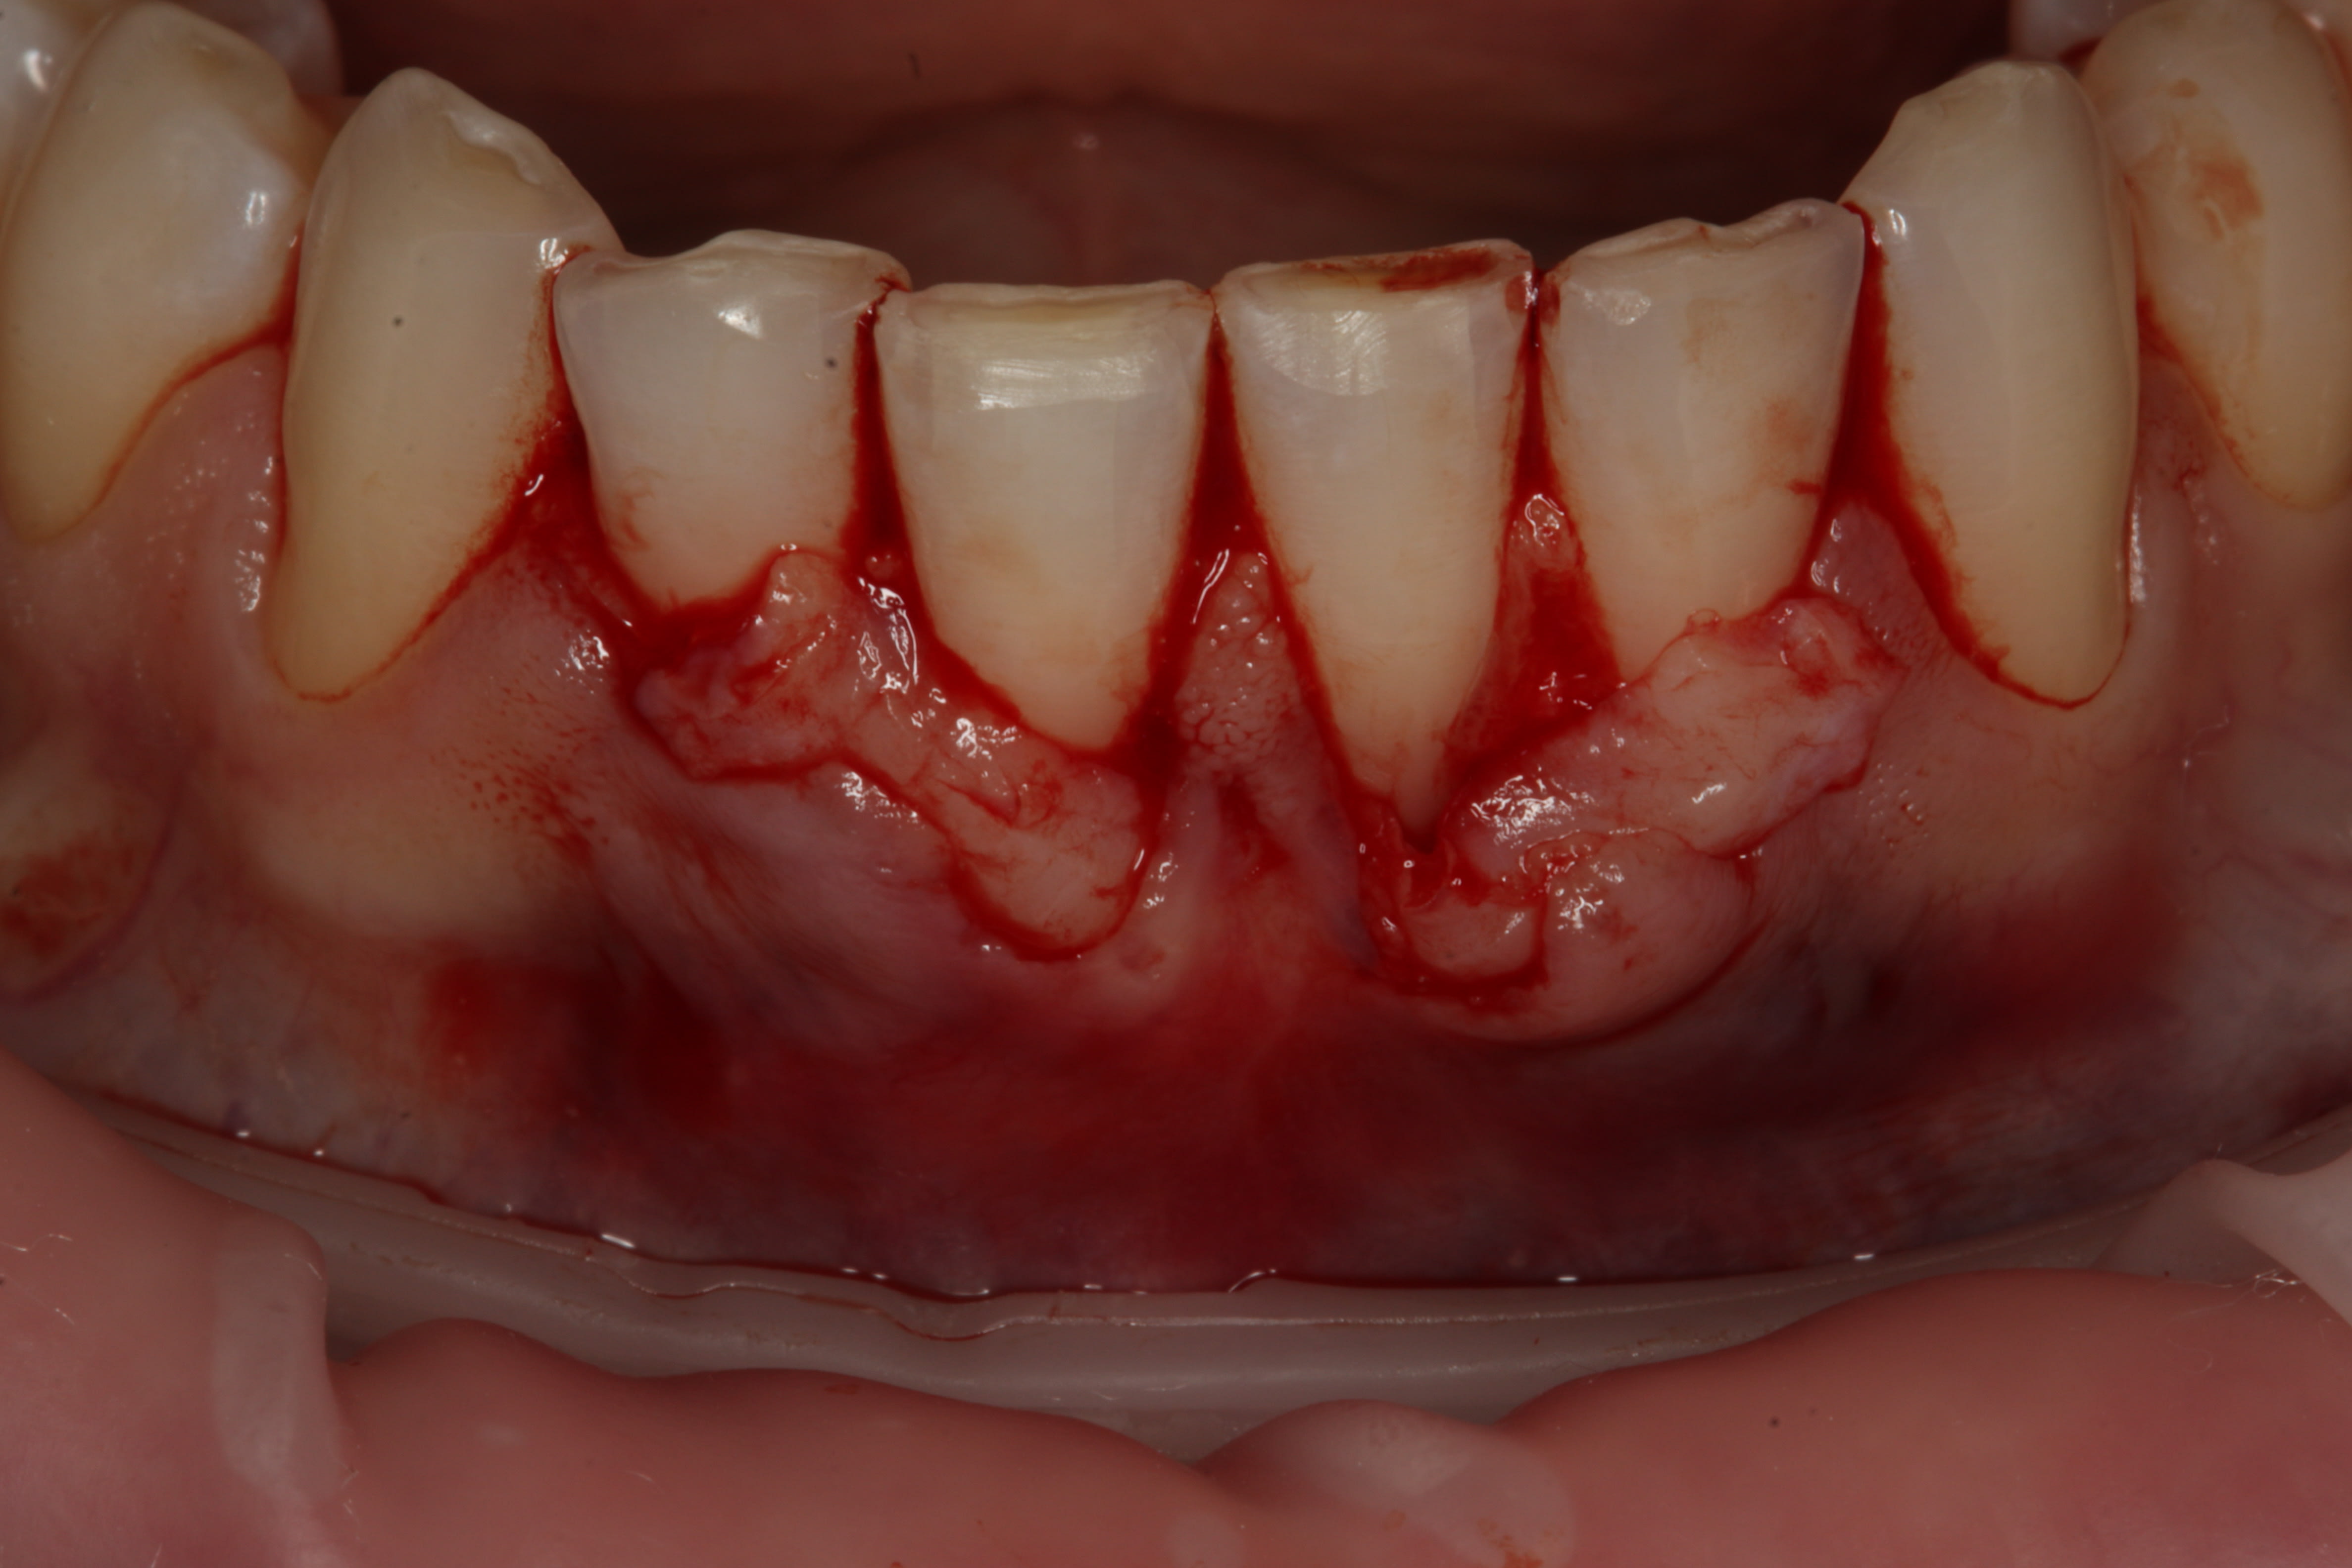

Cependant ici l'indication aurait plus été une technique avec une greffe épthélio-conjonctive en 1 ou 2 temps amha.

Car même si l'épaisseur de gencive attachée est plus importante que sa hauteur, ici c'est trop limite.

Une récidive sur 31m et 32m, voir 41m est à prévoir.

Pas d'accord avec toi pour la GEC

GEC dans un tissu mince comme ça c'est pas mieux, et doit faire du 2 temps, avec un résultat moche esthétiquement.

Récidive ??? non, au contraire, ça sera encore plus beau dans qq mois. Le biotype change avec l'ajout d'un tissu autogène dense comme celui utilisé. Je trouve pas ça limite du tout.